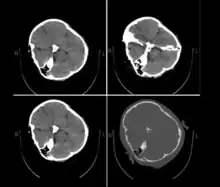

Published hospital pictures show Mahsa Amini bleeding from the ear and with bruises under her eyes. In an 18 September letter, Doctor Hossein Karampour (the top medical official in Hormozgan province), pointed out that such symptoms "do not match the reasons given by some authorities who declared the cause to be a heart attack... (they are instead consistent with) a head injury and the resulting bleeding."[64] This was also confirmed by alleged medical scans of her skull, leaked by hacktivists, showing bone fracture, hemorrhage, and brain edema.[10][65]

By 21 September, the hospital had released preliminary CT scans. Government supporters stated the CT scans showed psychological stress caused by a previous brain operation; critics stated the scans showed physical beating and trauma. The Iranian government stated Amini had a brain operation at the age of five.[67]